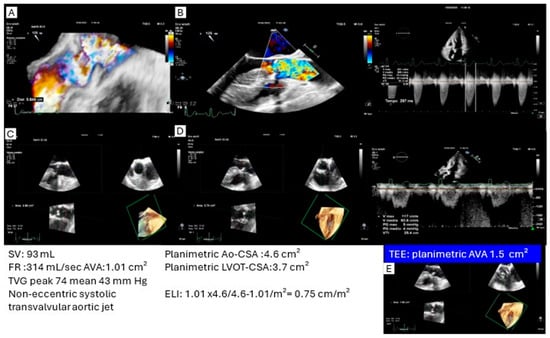

Algorithm for evaluation of high transvalvular aortic gradient. Ao ...